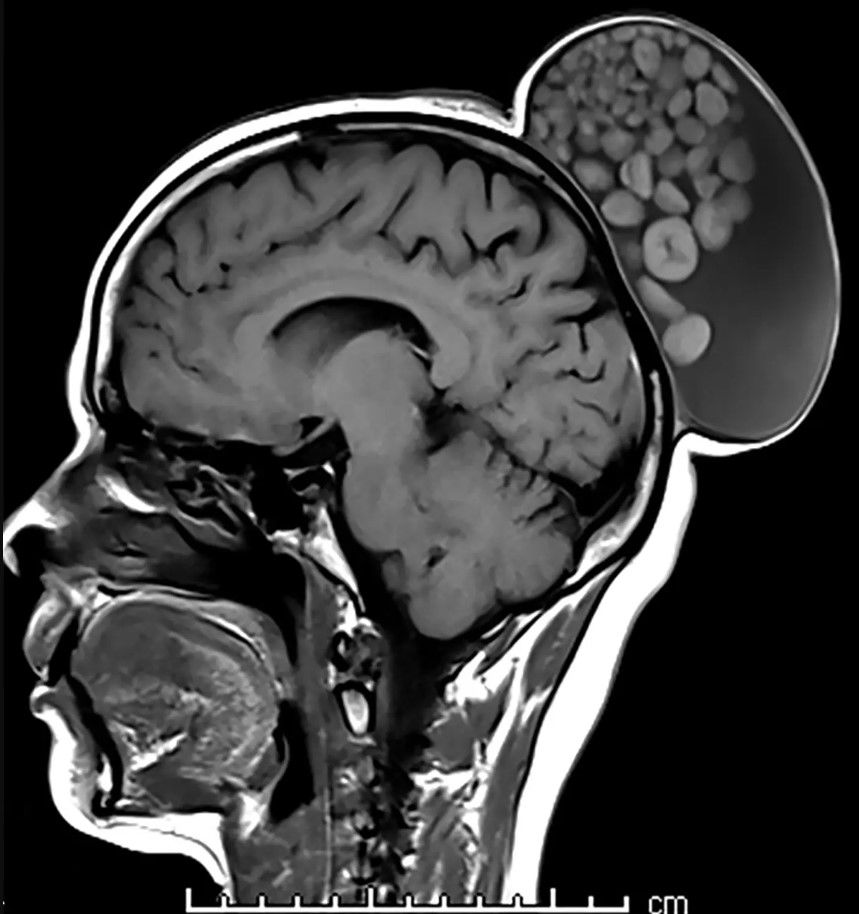

En Inglaterra, especialistas extirparon un quiste de 15 centímetros de la cabeza de una mujer india de 52 años. Al momento de la operación, el quiste aún presentaba pelos y unas esferas de grasa que parecían una “bolsa de canicas”, según consigna The New York Post.

Las pruebas realizadas indican que el quiste extirpado medía 15 cm de largo, 10 cm de ancho y 12 cm de alto. Los expertos también informaron que los tejidos que estaban dentro del quiste en la cabeza de la mujer eran de “diferentes tamaños”.